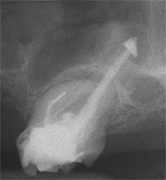

Aufbissempfindlichkeit an 33 veranlasste uns erstmalig in dieser Kieferregion zu röntgen. Mit grossen Augen sahen wir dann an, was uns auch ansah. Einen Knochendefekt dieser Grössenordnung mit seiner schaurigen Aura sieht man zum Glück nicht jeden Tag. Doch, obgleich das Alien dereinst Zahn 34 entsprang, war eine Behandlung nur am Zahn davor durchsetzbar. Dessen Wurzelfüllung erfolgte regulär nach 14 Tagen, neue Terminangebote aber wurden, weil angeblich nicht mehr nötig, verschmäht.

Keine 8 Wochen gingen noch in's Land, bis das mit Macht geschah, was lange schon erwartet war. Das Arbeitsprogramm bestand aus Eröffnung von Zahn 34 und einer Schwellung inkl. Drainage, am nächsten Tag dann noch Aufbereitung des Kanals mit Einlage. 2 Wochen später dann die Füllung plus einem als Resektion deklarierten Auslöffeln des Granu­lationsgewebes durch eine Mini-Öffnung, zu deren Verschluss eine Naht genügte.

3 Aufnahmen sind von 2001, die vierte vom Nov. 2006